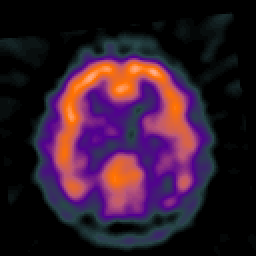

Alzheimer's disease: overlay -- Slice #35

[Home][Help][Clinical] Slice 35